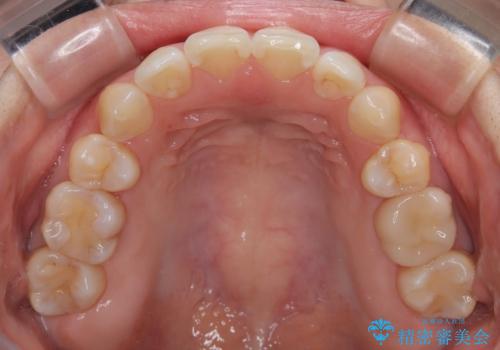

- 上下前歯の後戻りを気にして来院された患者様です。

インビザラインでの治療を希望されていて、デコボコの程度が中等度であり、安価なパッケージにて対応可能と判断されたため、インビザライン・モデレートを用いて矯正治療を行うこととしました。

インビザライン・モデレートは、製作できるアライナーの枚数に制限があるため、移動可能な量に限りがあるものの、インビザライン・ライトよりも枚数が多いため、幅広い症例に対応可能です。